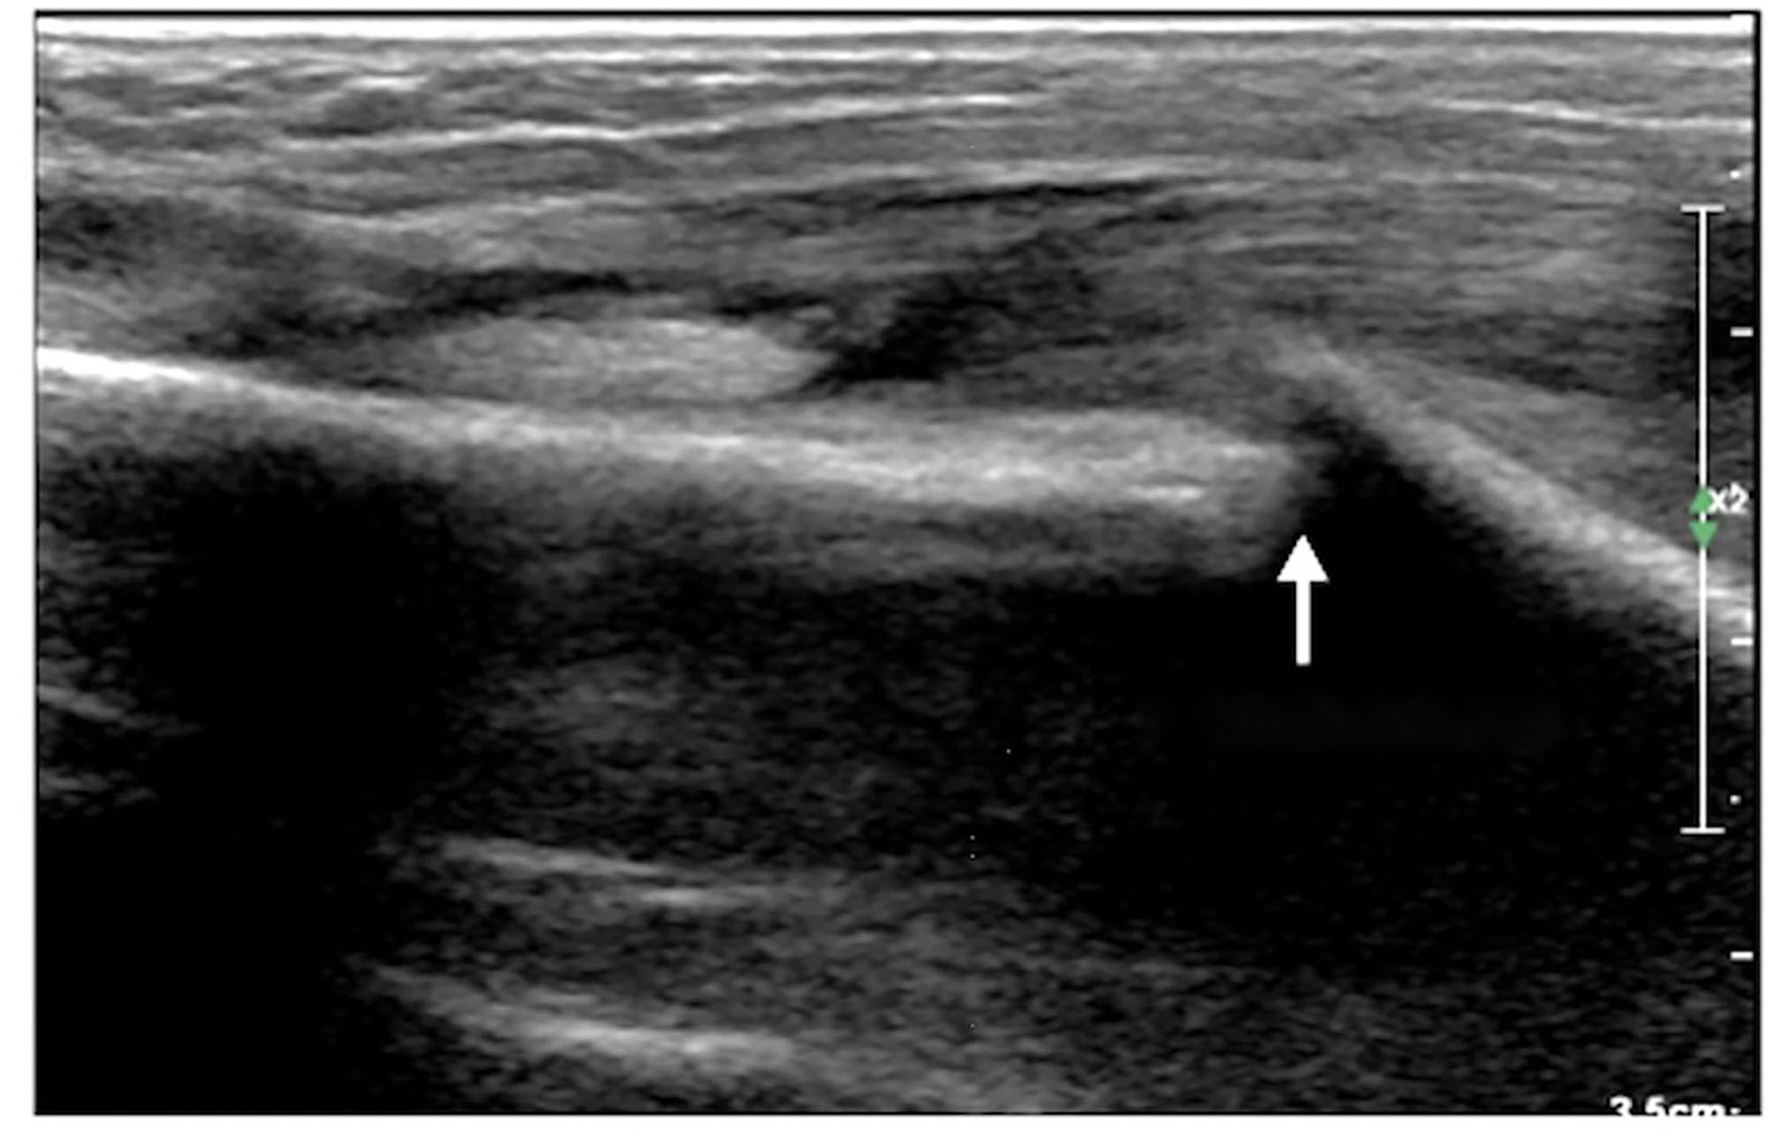

Figure 5

Rib fracture. The infant was G3P1, with a gestational age of 30+1 weeks and a birth weight of 1,370 g. The infant was born by Cesarean section due to placental abruption. After birth, the infant suffered from various diseases, such as respiratory distress syndrome, pneumonia, atelectasis, and calcium and phosphorus metabolism disorder, which was diagnosed as metabolic bone disease. Forty days after birth, an ultrasound examination found that the infant had a fracture in the fifth rib on the left side.